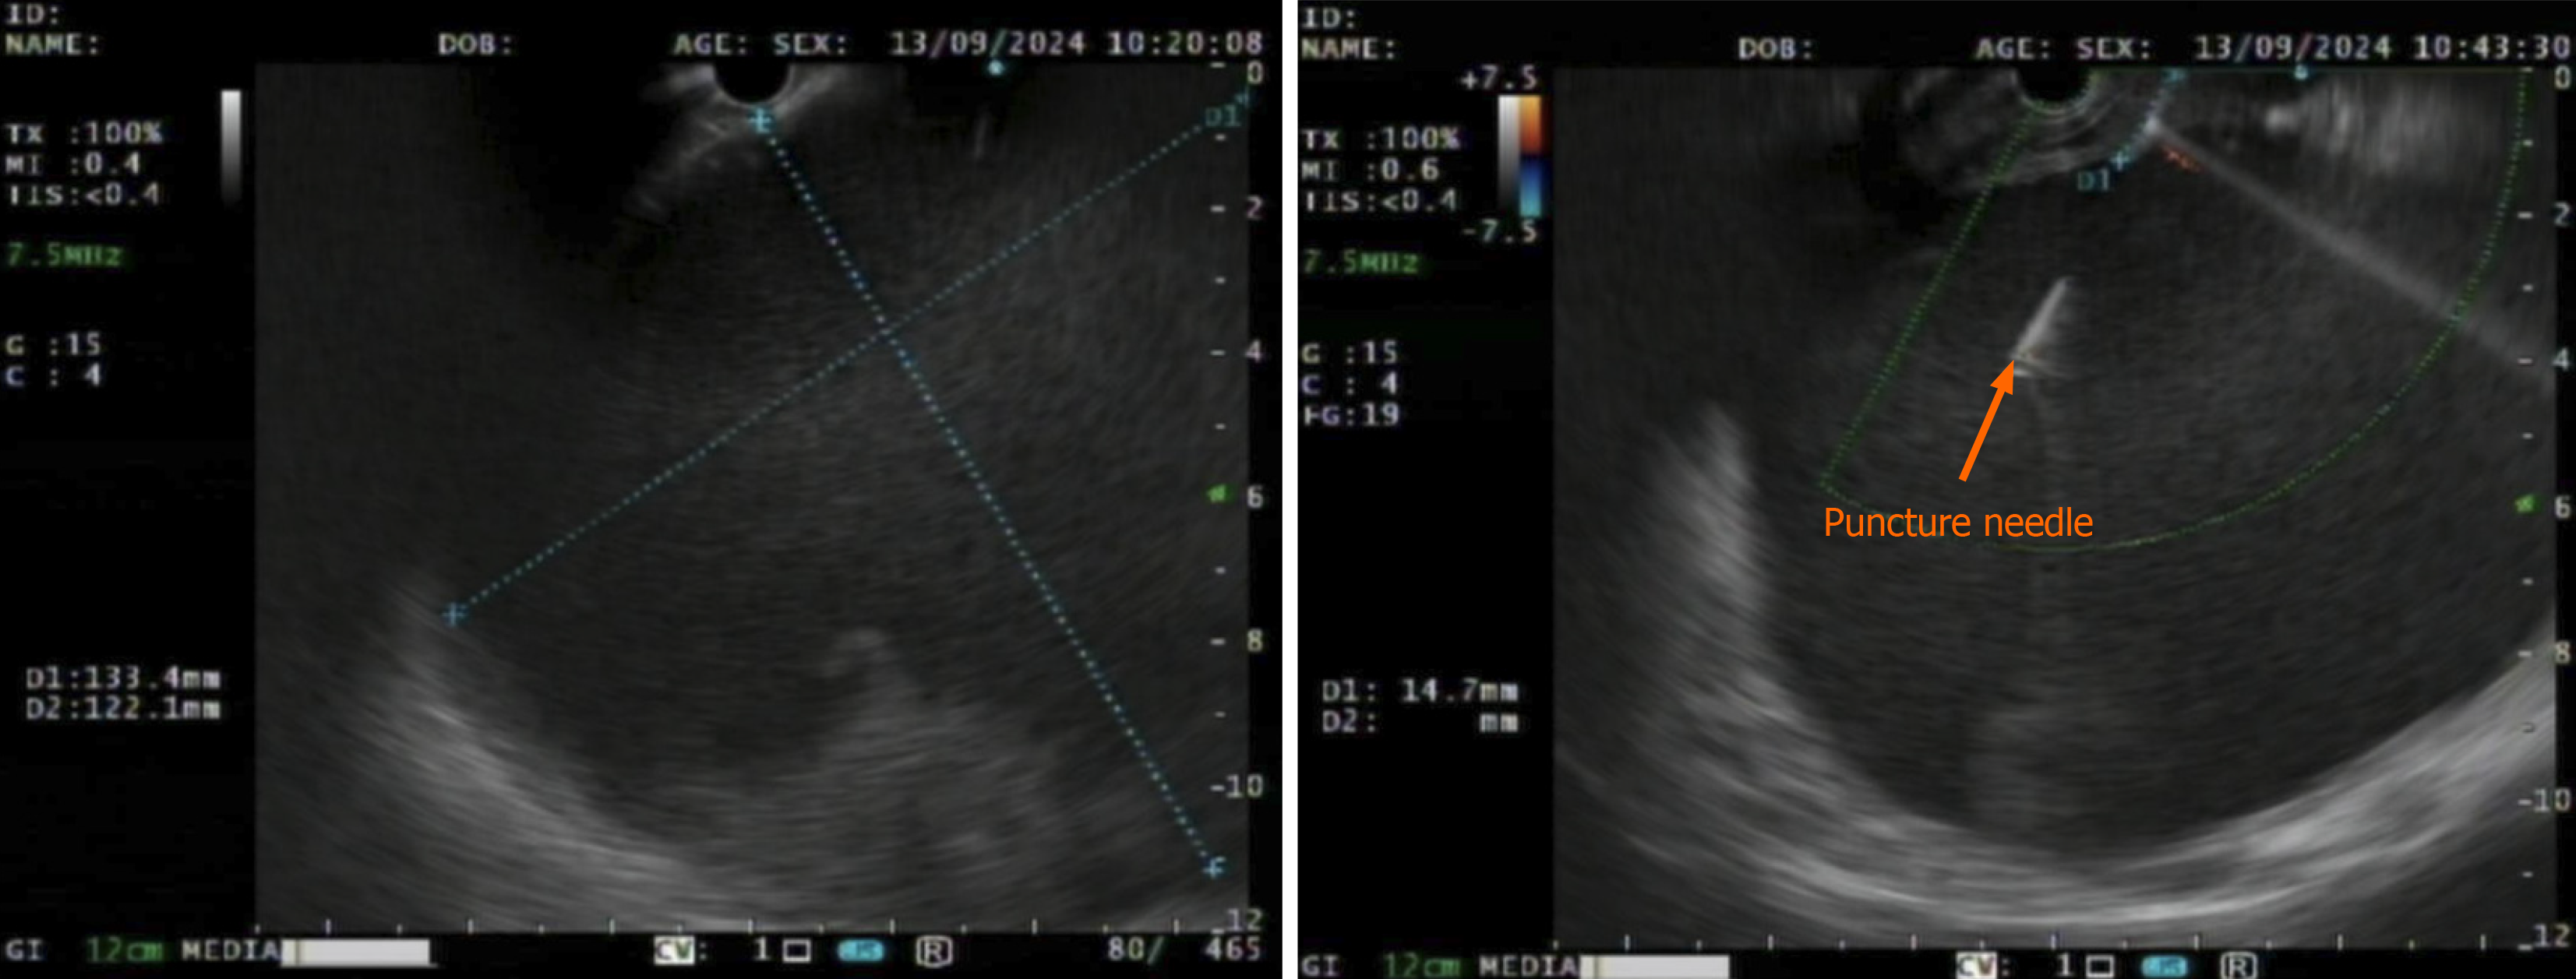

Under general anesthesia with endotracheal intubation, endoscopic ultrasound revealed a circular hypoechoic lesion in the body of the pancreas, with scattered areas of increased echogenicity (Figure 2). A 23G needle was utilized for puncture, yielding a coffee-like fluid. The puncture site was marked, and a Dual knife was employed to incise the gastric wall, exposing white, wall-like tissue. Upon aspiration with the puncture needle, a significant amount of coffee-like fluid was observed, prompting a deeper incision at the site, resulting in a substantial outflow of fluid (Figure 3). The endoscope was subsequently inserted into the cystic cavity to facilitate further aspiration, revealing a flocculent substance at the base. Hemostasis was achieved, and a gastric tube was placed (Figure 4).